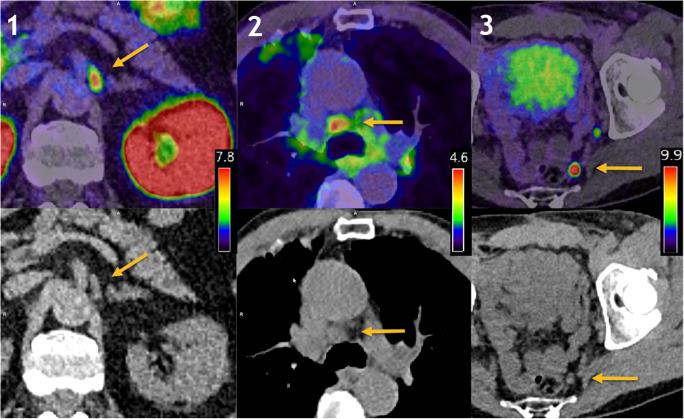

Four physicians retrospectively evaluated two matched cohorts of patients undergoing [Ga]Ga-PSMA-11 PET/CT on a digital (dPET/CT n = 65) or an analogue scanner (aPET/CT n = 65) for recurrent prostate cancer between 11/2018 and 03/2019. The number of equivocal and pathological lesions as well as the frequency of discrepant findings and the interrater reliability for the two scanners were compared.

dPET/CT detected more lesions than aPET/CT (p < 0.001). A higher number of pathological scans were observed for dPET/CT (83% vs. 57%, p < 0.001). The true-positive rate at follow-up was 100% for dPET/CT compared to 84% for aPET/CT (p < 0.001). The proportion of lesions rated as non-pathological as a total of all PSMA-avid lesions detected for dPET/CT was comparable to aPET/CT (61.8% vs. 57.0%, p = 0.99). Neither a higher rate of diagnostically uncertain lesions (11.5% dPET/CT vs. 13.7% aPET/CT, p = 0.95) nor discrepant scans (where one or more readers differed in opinion as to whether the scan is pathological) were observed (18% dPET/CT vs. 17% aPET/CT, p = 0.76). Interrater reliability for pathological lesions was excellent for both scanner types (Cronbach's α = 0.923 dPET/CT; α = 0.948 aPET/CT) and interrater agreement was substantial for dPET/CT (Krippendorf's α = 0.701) and almost perfect in aPET/CT (α = 0.802).

A higher detection rate for pathological lesions for dPET/CT compared with aPET/CT in multiple readers was observed. This improved sensitivity was coupled with an improved true-positive rate and was not associated with increased diagnostic uncertainty, rate of non-specific lesions, or reduced interrater reliability.